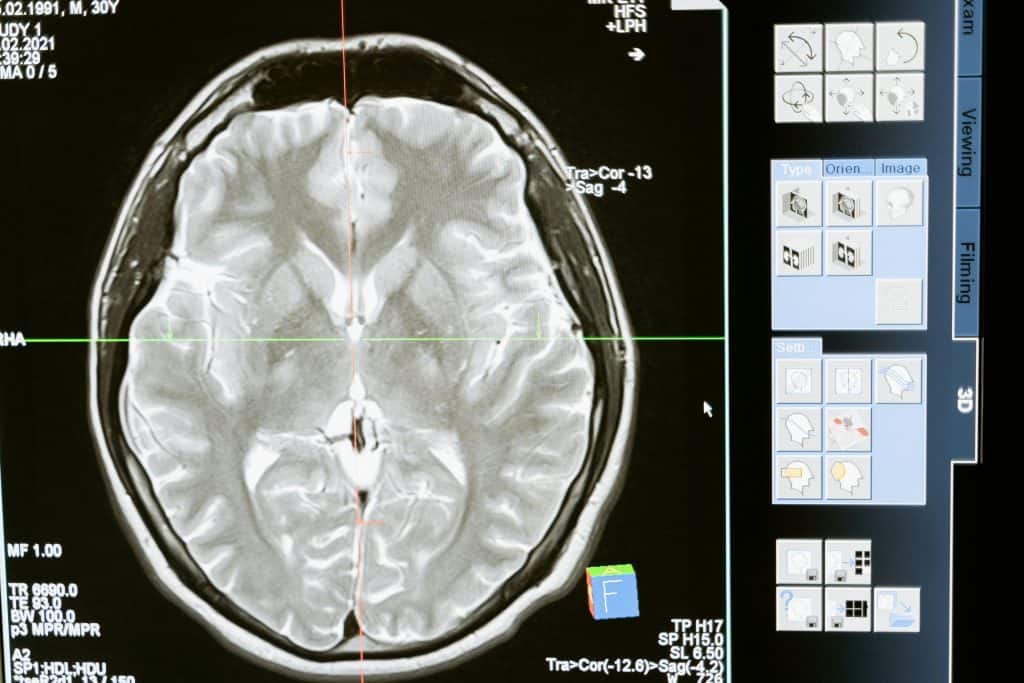

Entenda por que um cérebro grande não é sinônimo de inteligência. Imagem: Talaj / iStock

Exame de imagem mostra o cérebro humano (Imagem: MART PRODUCTION / Pexels)